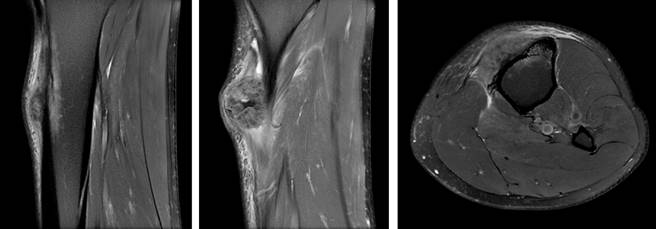

Three months later MR was repeated showing increase in size 42 × 40 × 27 mm and small areas of necrosis. Large attachment to the anterior periosteum remains with exophytic growth contacting the skin (Figure 3). With new imaging a third biopsy was performed guided with ultrasound. It showed trabecular osteoid areas that converge and areas of spindle cells with moderate cellular atypia, that suggested cPOS or HGSO.

Figure 3: MR image of the tumor showing growth compared with previous image. Contact with the skin can be noted.